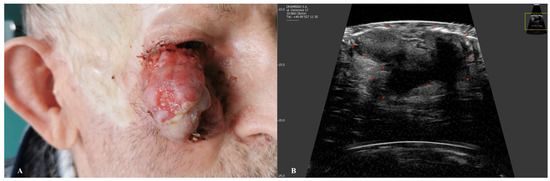

2. Basal Cell Carcinoma

| Basal Cell Carcinoma | Oval, hypoechogenic lesion with well-defined borders. Hyperechoic spots (“cotton flower” pattern) may be present. Poor vascularization on Doppler. |